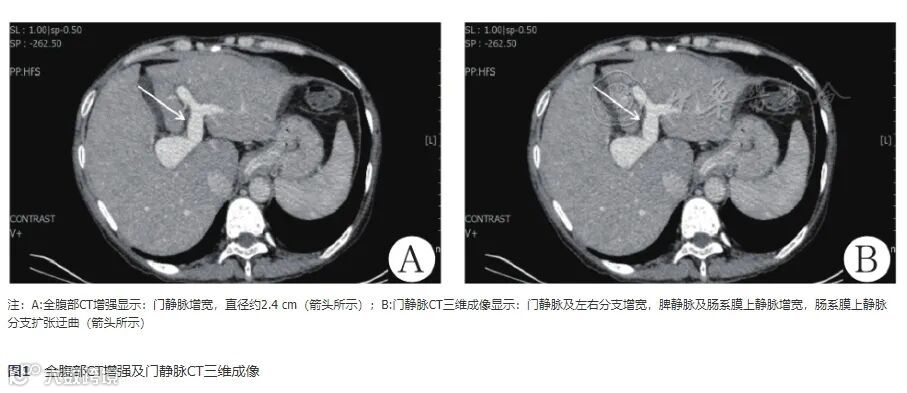

赵本田, 王尧, 江晨, 辛永宁. 特发性门静脉高压症1例 [J] . 中华肝脏病杂志, 2024, 32(1) : 76-79. DOI: 10.3760/cma.j.cn501113-20231129-00249.